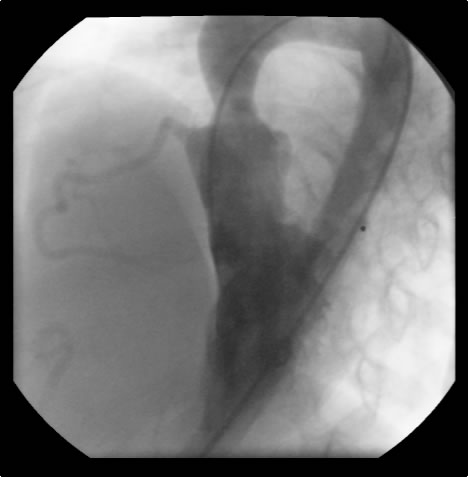

Brom’s three-patch aortoplasty is indicated for the repair of supravalvar aortic stenosis, which can occur as an isolated defect or as a part of Williams syndrom [1]. This syndrome is characterized by supravalvar aortic stenosis, elfin craniofacial features, peripheral pulmonary artery stenosis, and hypercalcemia. The underlying cause is a loss of function mutation of the elastin gene on chromosome 7q11.23. These patients will have a systolic cardiac murmur and two-dimensional echocardiography can establish the diagnosis. Cardiac catheterization is indicated to evaluate the status of the coronary arteries and assess the pulmonary arterial tree for related peripheral stenosis.

Indications for surgery include symptoms of diminished exercise tolerance, syncope, or angina. Other indications would include 1) systolic ascending aorta gradient greater than 50 mm Hg, 2) aortic valve insufficiency, or 3) evidence of compromised coronary artery perfusion. These patients should undergo surgery at a relatively early age because of the detrimental effect of the high proximal aortic pressure on the coronary arteries with the possibility for accelerated atherosclerotic changes. These patients typically have a thickening of the aortic wall at the sinotubular junction. This abnormal thickening may extend into the ascending aorta and even into the aortic arch. In some patients, this abnormal thickening creates stenosis of the coronary ostium.

An asymptomatic, 5-year-old, 18-kg boy known by genetic testing to have Williams syndrome on physical examination had a IV/VI harsh systolic ejection murmur and no diastolic murmur. Preoperative echocardiogram showed an aortic root dimension of 2 cm and the dimension at the level of stenosis in the ascending aorta was 8 mm. Peak echocardiogram gradient was 70 mm Hg with a cardiac catheterization gradient of 50 mm Hg. The child had no peripheral pulmonary artery stenosis.